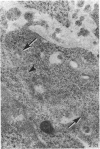

Renin-containing cells in fetal adrenal glands of the mouse were investigated with the protein A-gold immunocytochemical technique. On Day 14 of gestation, a small number of specific granules were weakly immunoreactive and were distributed in the Golgi region. Sometimes, apparent exocytosis of gold-labelled particles could be seen opening into the extracellular space. On Day 16 of gestation, numerous gold particles were demonstrated in the Golgi region as well as in the specific secretory granules. Immunoreactivity of the specific granules was increased as compared with Day 14, though some granules were observed to have no reaction with the antibody. On Day 18 of gestation reactivity for renin decreased, while a few clustered immunoreactive granules were demonstrated just beneath the cell membrane. No gold particles were observed in the Golgi apparatus during this period and more granules negative for renin were noted than on Day 16 of gestation. These results suggest that renin is produced and released temporarily by adrenal cortical cells in the late fetal life of the mouse.